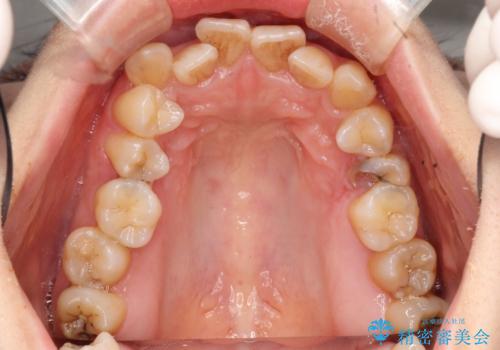

初診時の歯並びの状態としては、上下ともに前歯部の中等度のがたつきがあり、下の前歯は本来生えるはずの歯が2本生まれつき欠損している状態でした。

また、上顎の歯は虫歯で歯冠が崩壊してしまって保存不可能な歯がありました。